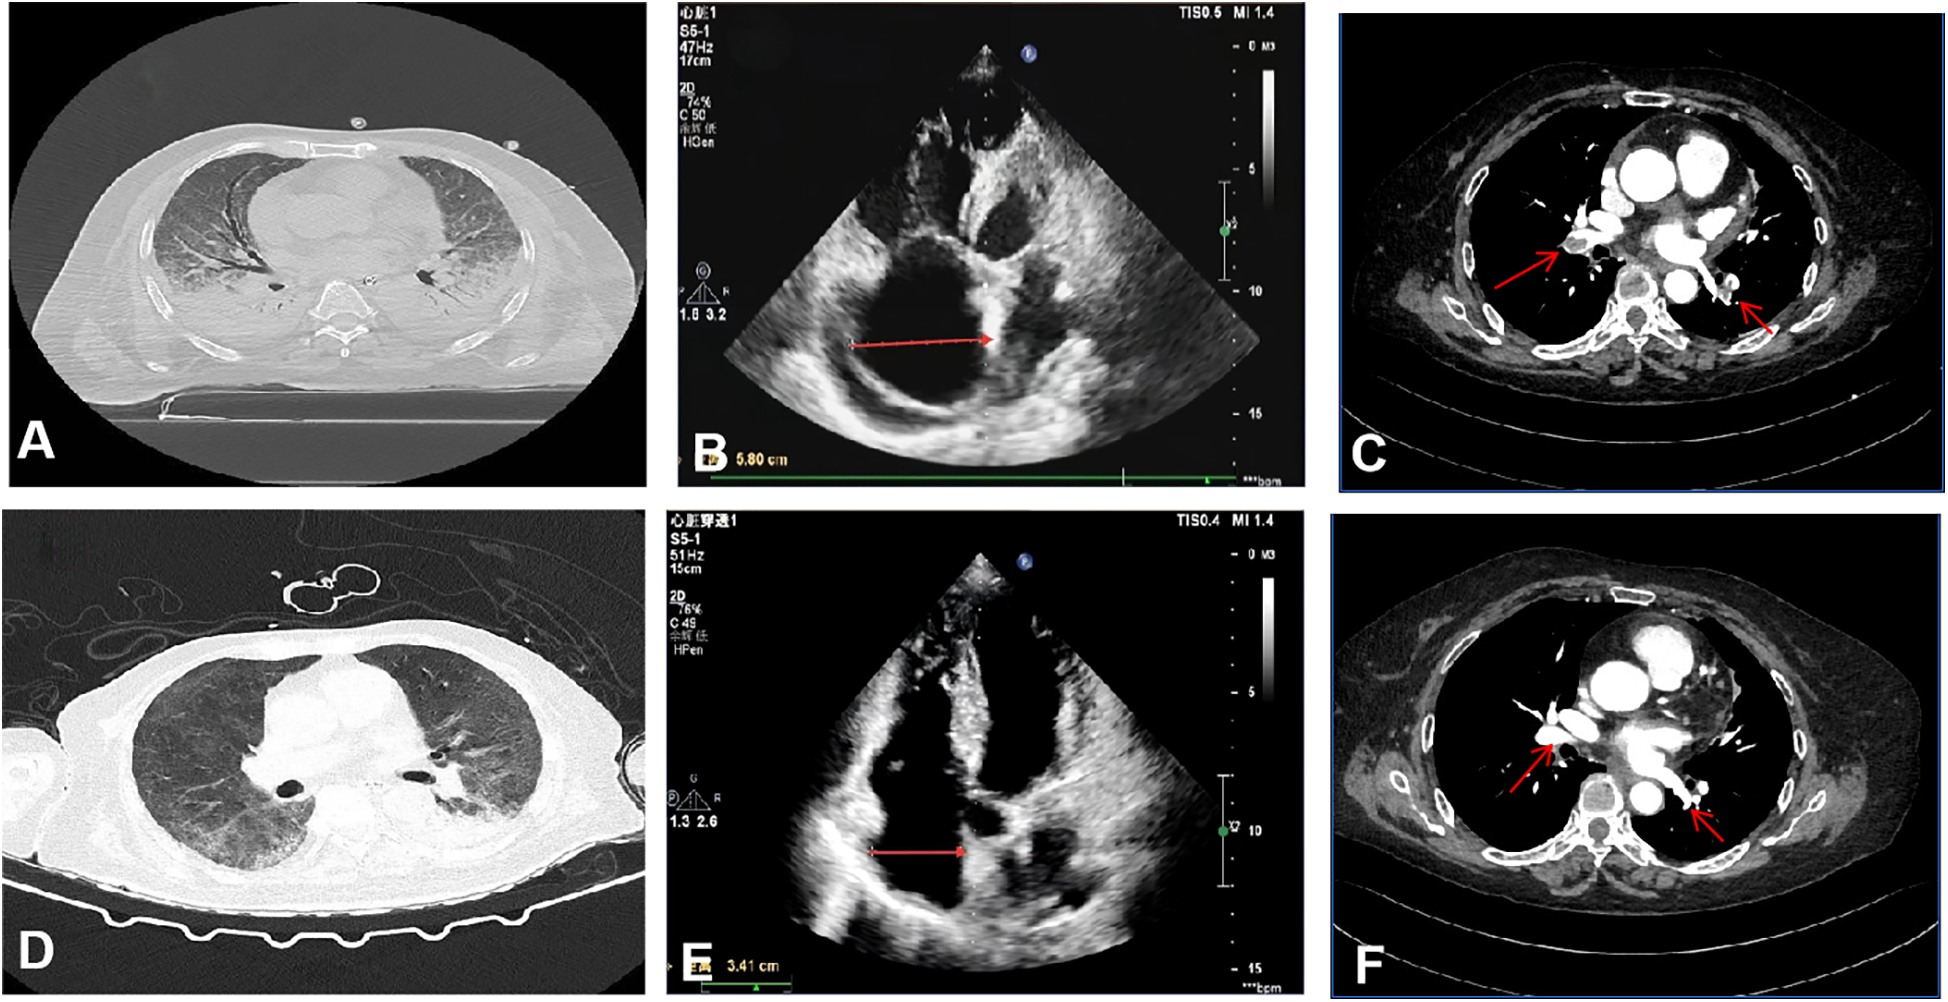

Blood gas analysis showed PH 7.38 (Reference Range 7.35–7.45), PaCO2 30.08 (Reference Range 35–45) mmHg, PaO2 47.84 (Reference Range 80–100) mmHg, lactate 5.66 (Reference Range 1–1.7) mmol/L, and an oxygenation index of 78.4 mmHg (FiO2 0.61). Troponin was 0.125 (Reference Range 0–0.04) ng/mL, NT-ProBNP was 3,735.2 (Reference Range 0–900) pg/mL, and a throat swab PCR test was positive for influenza A H1N1 nucleic acid. Pulmonary CT revealed interstitial infection in both lungs (Figure 1A). Lower extremity ultrasound showed hypoechoic areas within the intramuscular veins of both lower legs, and echocardiography revealed right ventricular enlargement (Figure 1B). Left ventricular systolic function was preserved.

Figure 1

Imaging and echocardiographic findings before and after treatment. (A–C) Pre-treatment: (A) Chest CT shows bilateral pulmonary consolidation and interstitial infiltrates. (B) Transthoracic echocardiography reveals right atrial enlargement (transverse diameter 5.8 cm). (C) CT pulmonary angiography demonstrates extensive bilateral pulmonary embolism. (D–F) Post-treatment: (D) Chest CT indicates resolution of pulmonary consolidation and marked improvement of interstitial opacities. (E) Echocardiography shows significant reduction in right atrial size (transverse diameter 3.41 cm). (F) CT pulmonary angiography confirms substantial reduction in thrombus burden.

The patient was diagnosed with severe H1N1 viral pneumonia complicated by type I respiratory failure and heart failure, based on integrated clinical, radiological, and laboratory findings. The patient was treated with antibiotics (Empirically administered Cefoperazone-Sulbactam 3 g q8h combined with Moxifloxacin 0.4 g qd), antiviral therapy (Oseltamivir 75 mg bid), anti-inflammatory treatment (Methylprednisolone 40 mg bid), anticoagulation (6000IU QN), non-invasive ventilator-assisted ventilation, and high-flow nasal cannula oxygen therapy (HFNC). On January 15, 2024, the patient's condition deteriorated, with the oxygenation index falling to 48 mmHg, necessitating endotracheal intubation, invasive mechanical ventilation, and prone positioning. Despite these interventions, hypoxemia persisted. Elevated D-dimer levels (6.79 mg/L, Reference Range <0.5) prompted computed tomography pulmonary angiography, which revealed extensive bilateral pulmonary emboli (Figure 1C). Given the critical clinical status, a multidisciplinary team recommended veno-arterial extracorporeal membrane oxygenation (VA-ECMO) combined with percutaneous thrombectomy. On January 16, VA-ECMO was initiated percutaneously via the right femoral vein (21 Fr) and left femoral artery (17 Fr) using a Maquet HLS Set Advanced circuit. Initial settings included a pump speed of 2,500–3,000 rpm, titrated to maintain a blood flow of 2.0–3.0 L/min, and a sweep gas flow of 3.0 L/min with an FiO2 of 0.8. A standardized anticoagulation protocol with unfractionated heparin (3,000-unit bolus followed by 750 units/hour infusion) was used, targeting an ACT of 180–200 s. Meticulous catheter site care and daily surveillance for circuit thrombosis or limb ischemia were performed, enabling an uneventful ECMO course. Percutaneous mechanical thrombectomy was performed subsequently. Angiography revealed extensive filling defects involving the LA1, RA8, RA7, RA4, RA5, RA1 and RA2 segmental arteries. Following thrombus aspiration using an Indigo aspiration system, repeat pulmonary arteriography demonstrated restored patency with robust bilateral pulmonary arterial opacification, confirming successful reperfusion. The patient's oxygenation index immediately rose to 90 mmHg postoperatively. On January 23, after the above treatments and supportive care, the patient's oxygenation level significantly improved, reaching 206.5 mmHg. With pulmonary CTA showing a reduction in thrombi and subsequent echocardiography confirming a diminished right atrial size (Figures 1E,F), the patient was successfully weaned from ECMO support. On January 31, Bronchoalveolar lavage fluid cultures later identified multidrug-resistant Acinetobacter baumannii (Multidrug-Resistant), leading to targeted antibiotic therapy with polymyxin 150 mg q12h combined with Tigecycline 50 mg q12h (with an initial loading dose) until discharge. By February 13, follow-up imaging demonstrated significant resolution of pulmonary infiltrates (Figure 1D), and the patient was discharged in stable condition. (See timeline of key interventions and clinical milestones in Table 1, change of biomarker in Table 2).